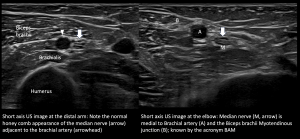

Arm: In the arm, the median nerve traverses between the biceps brachii and brachialis adjacent to the brachial artery. There are no major branches from the median nerve in the arm.

The median nerve appears round to ovoid in the short axis plane with hypoechoic internal fascicles against a background of hyperechoic interfascicular epineurium, which in turn is surrounded by an external echogenic epineurium giving it a honeycomb appearance. In the long axis, the nerve has a fibrillary pattern. No increased vascularity is demonstrated on the Doppler study [3,5].